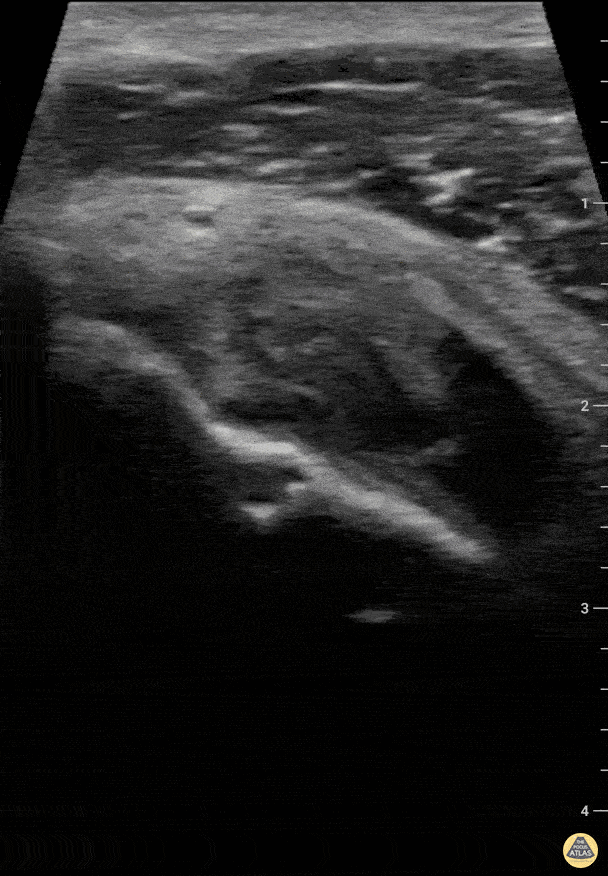

Musculoskeletal - Partial bicep tendon tear Short

Patient presented with pain localized to the right humeral neck after lifting a heavy object and feeling a "pop" sensation. Negative "Popeye" sign and preserved strength in elbow flexion. Effusion was noted in the bicipital groove on both transverse and longitudinal views. In addition, on longitudinal view the ends of the biceps tendon were noted to remain in tension. Charles Jang, EM PGY-3